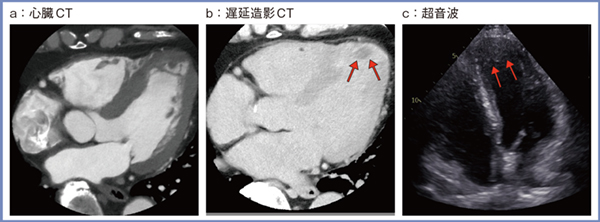

実際の症例を提示する。症例1は左室前壁の陳旧性心筋梗塞症例で,PIQEにて梗塞が高吸収域として明瞭に描出されている(図2↓)。症例2は60歳代,男性,狭心症疑い症例(図3)で,心臓CTにて左冠動脈前下行枝の高度狭窄と心尖部に構造物を認めた(a)。遅延造影CTでは,梗塞を示す白い領域の表面に黒い領域が描出され(図3 b↑),超音波検査にて心尖部の血栓が確認された(c↑)。

図3 症例2:狭心症疑い